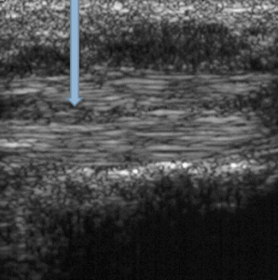

| In an ultrasound, what colour is bone, tendon and water (oedema)? | Bone = white Tendon = grey Water = black |

| What does the arrow indicate? | A cleft (tear) in the tendon |

| What does the red arrow show? What does the yellow arrow show? | Red arrow = fluid Yellow arrow = tendon tear |

| What does the arrow indicate? | Fluid |